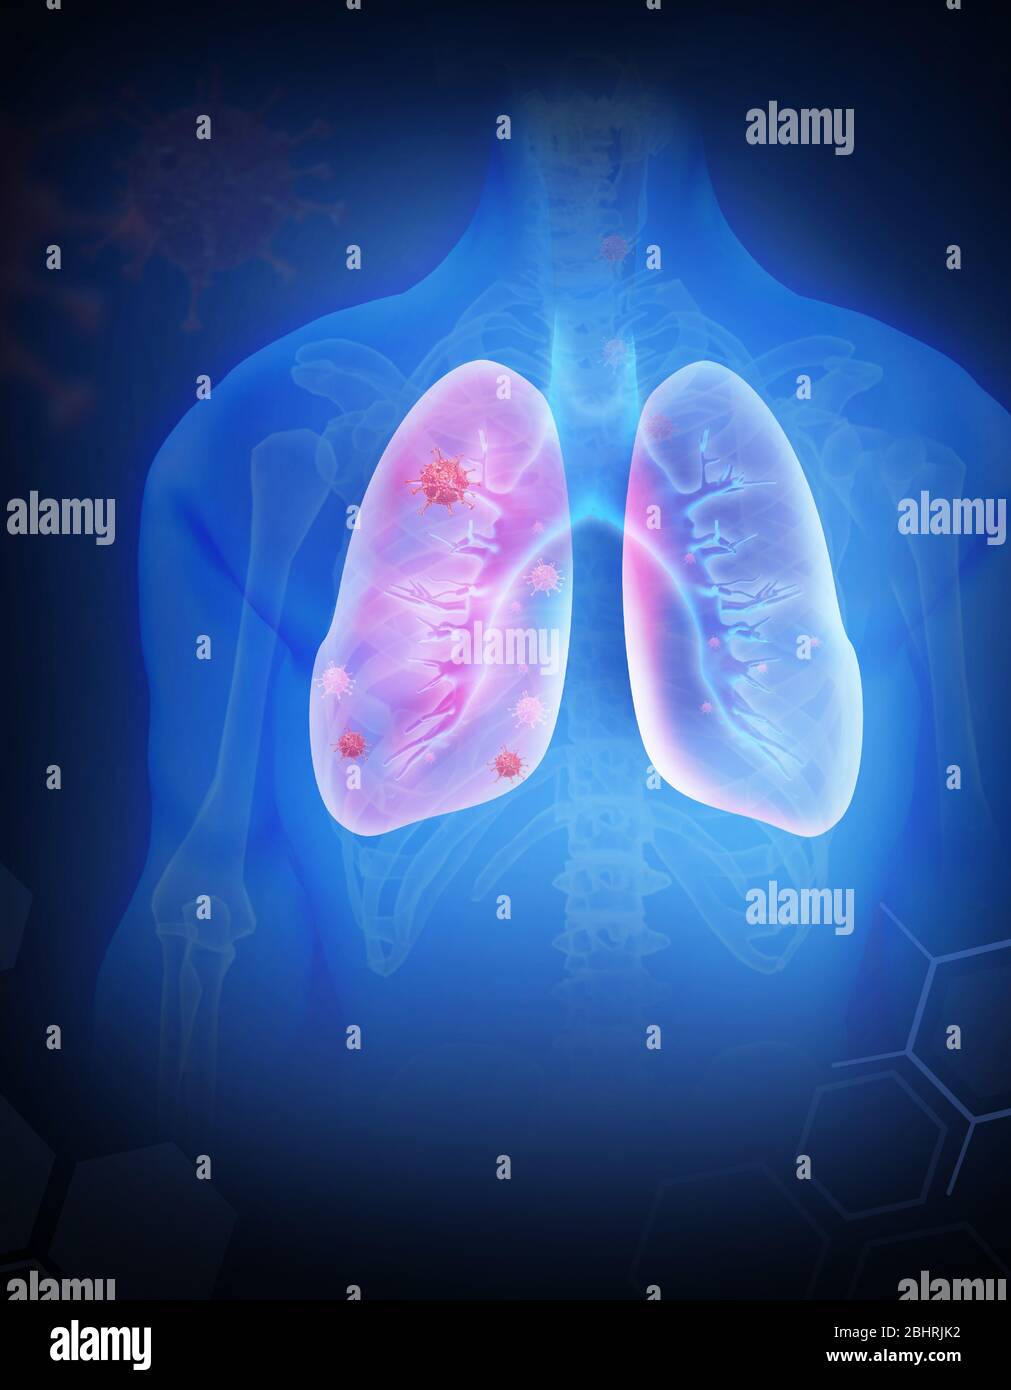

RF2BHRJK2–coronavirus la grippe comme cas dangereux de grippe comme une pandémie. Gros plan du virus du microscope. rendu 3d.

RF2BHB9Y4–Poumons infectés par des virus illustration vectorielle. Concept d'infection du coronavirus

RF2CX064R–Concept de symptômes du coronavirus chinois et de la pneumonie. Illustration vectorielle des poumons humains infectés par le virus 2019-nCoV. Diagnostic médical et preventio